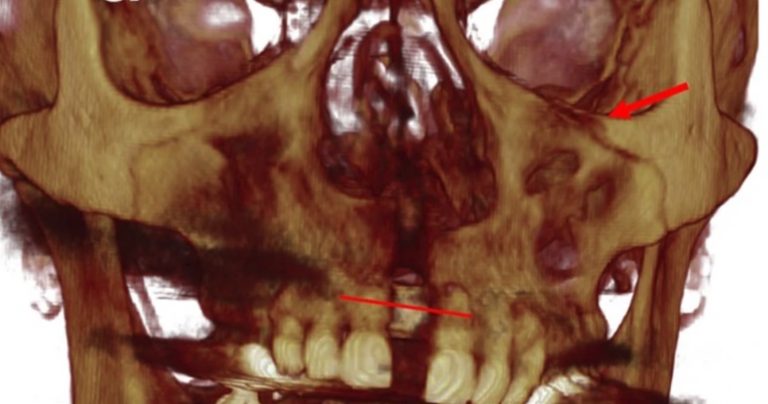

Tratamiento ortopédico de una maloclusión de clase III con mordida cruzada anterior profunda y discrepancia transversal

El artículo que compartimos el día de hoy con uds se llama Orthopedic Management of a Class III Malocclusion With Deep … [Leer más...] acerca de Tratamiento ortopédico de una maloclusión de clase III con mordida cruzada anterior profunda y discrepancia transversal